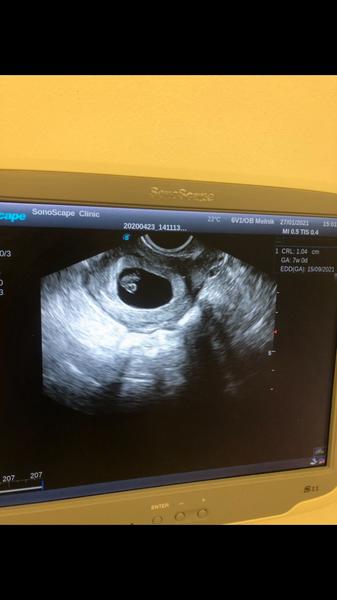

@fialka444 7+0